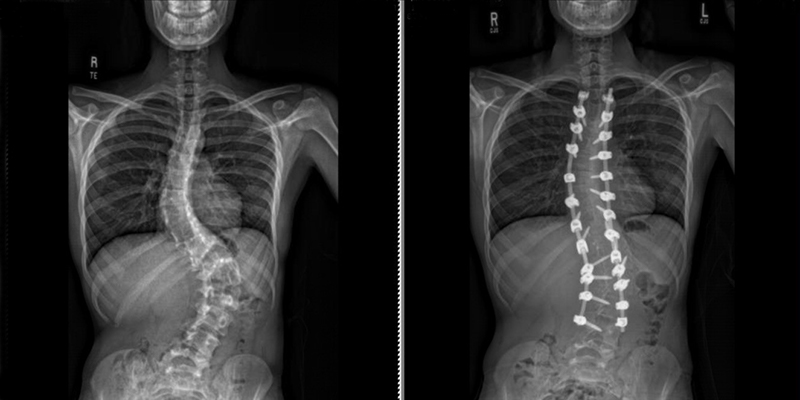

Research background: Using gabapentin for posterior spinal fusion recovery

Orthopedic specialists often recommend posterior spinal fusion surgery as a treatment option for patients with severe adolescent idiopathic scoliosis. Doctors have found that gabapentin, part of multi-modal pain management after surgery, is successful in adults and adolescents who undergo posterior spinal fusion surgery. The associated benefits include: